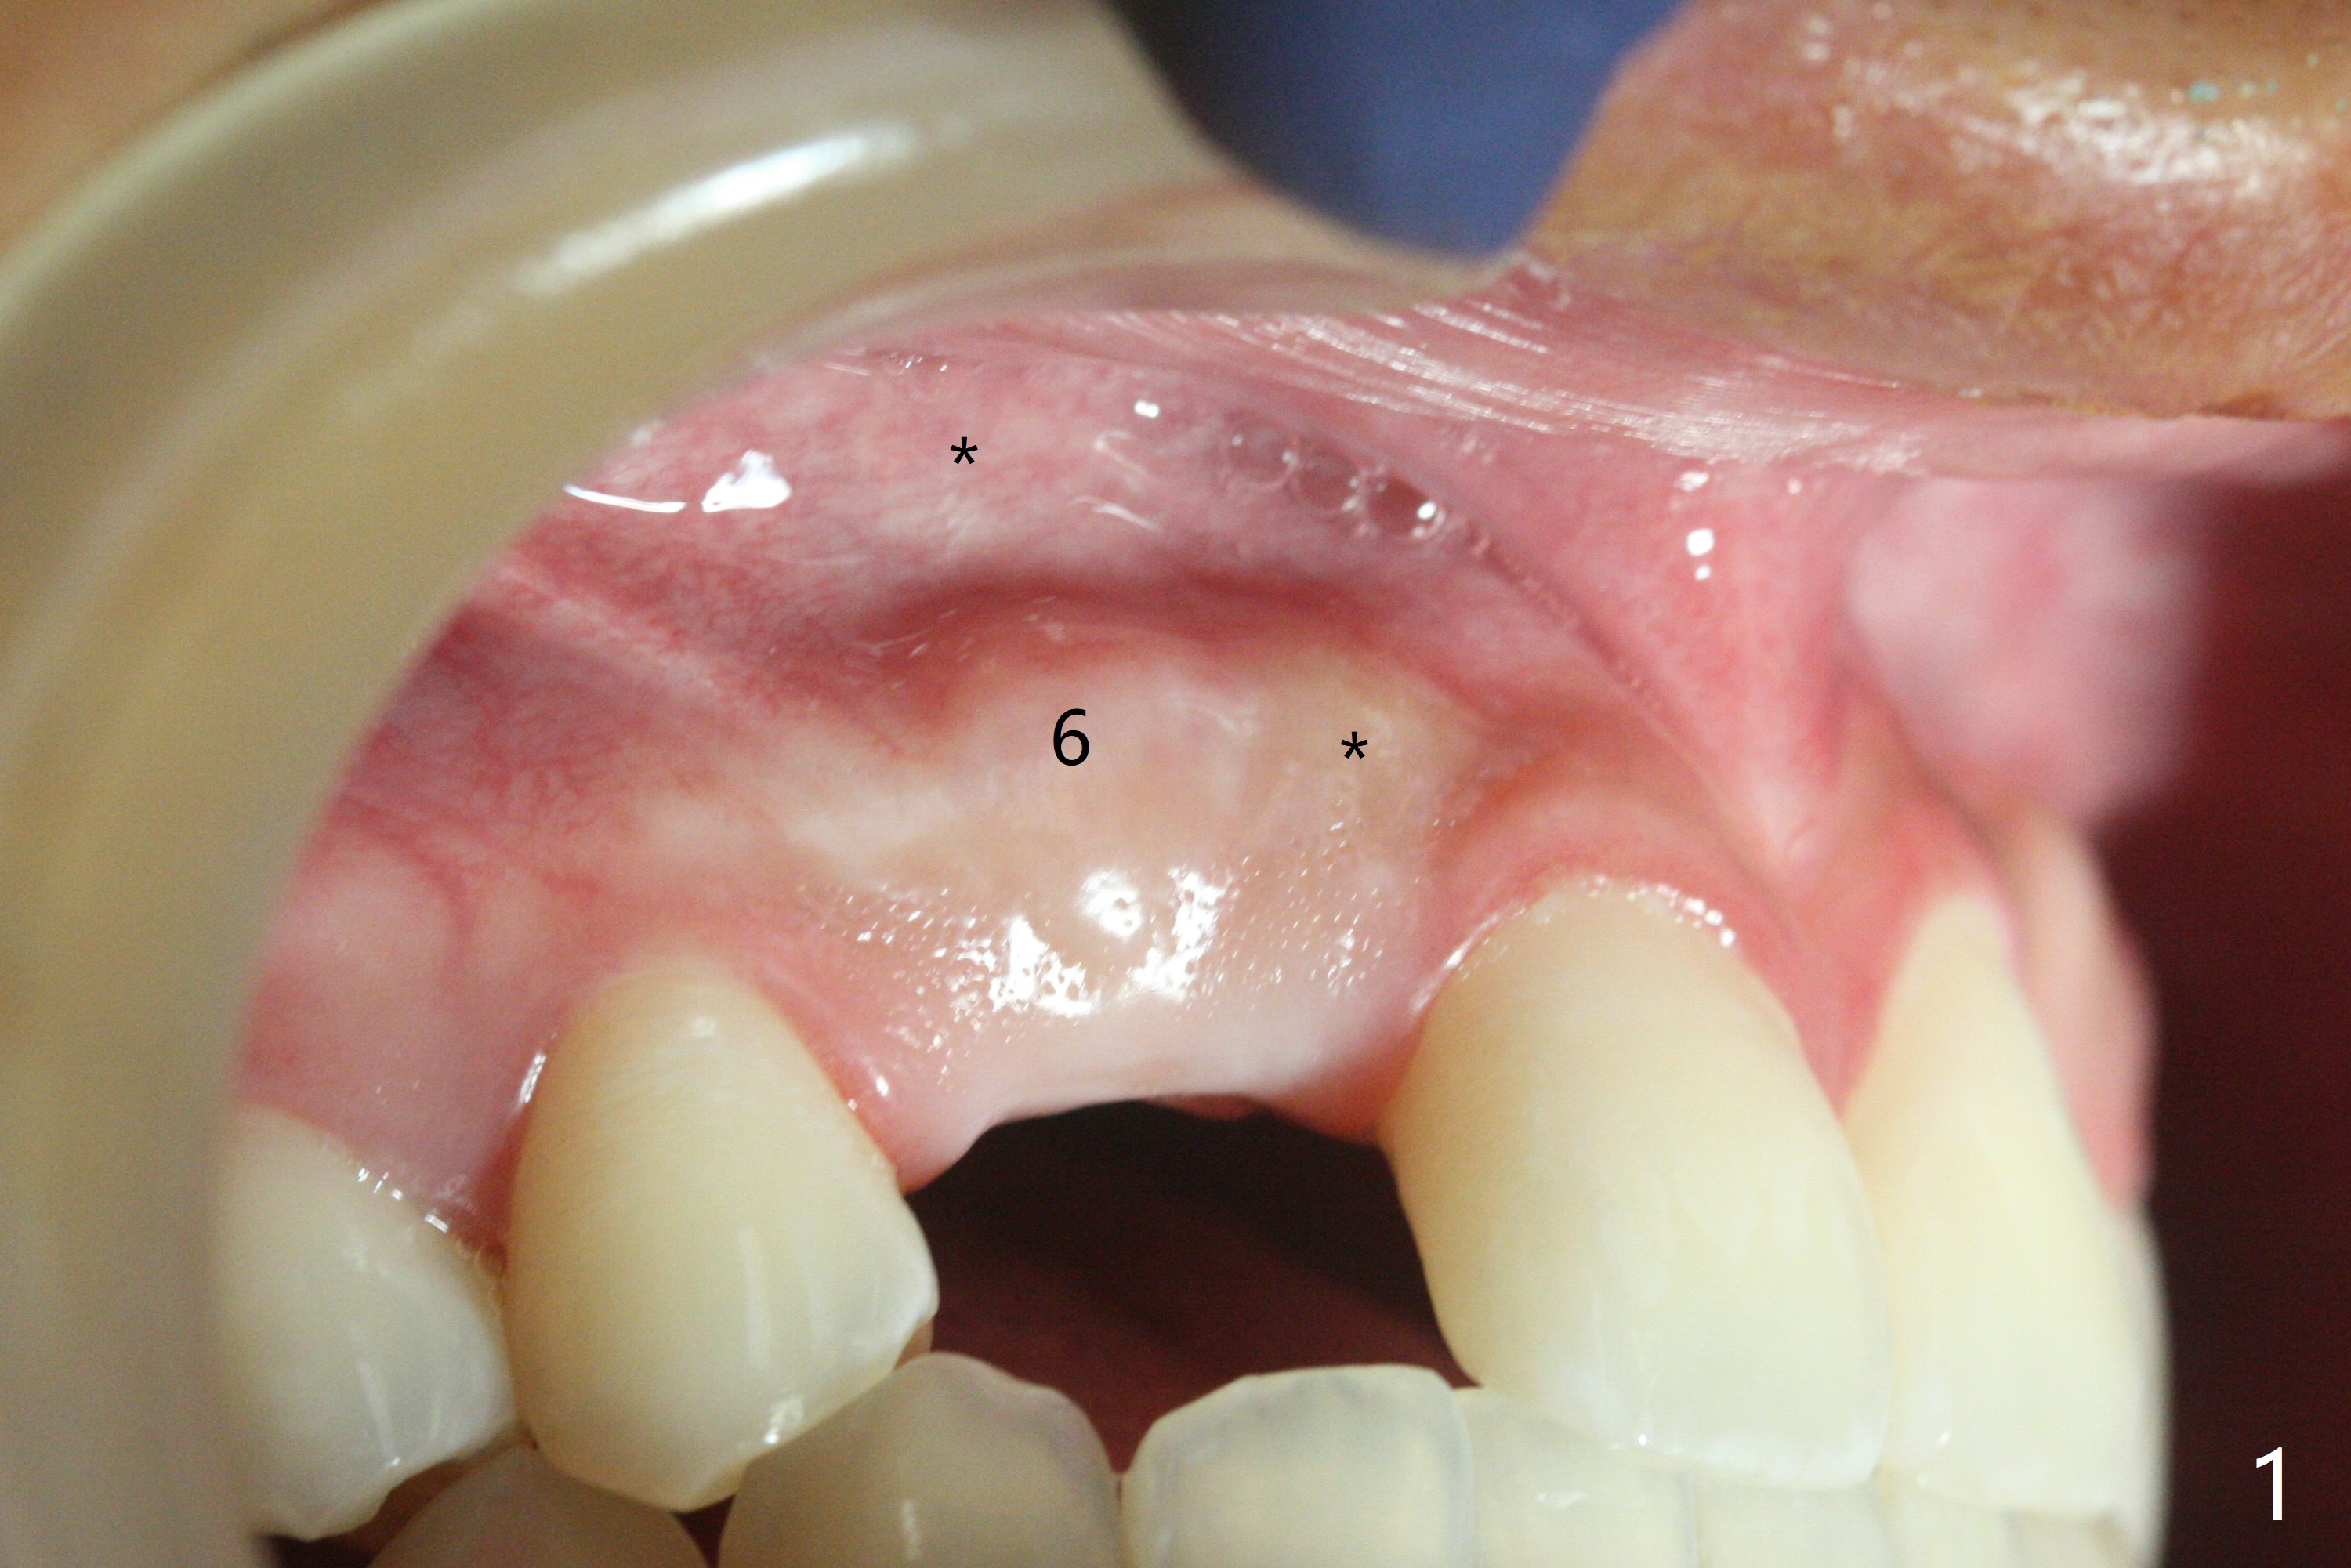

18岁男,本月底到外州上大学,急于十九岁前完成治疗,保险可以多付些。术前检查显示双侧尖牙(图一,二 6,11)根尖,侧切牙牙槽嵴萎缩(*),尖牙、侧切牙之间颊侧做垂直切口,骨膜下潜行分离,在尖牙根尖隧道植骨,然后使用导板,植入窄植体(图四至六),接近或者穿过上颌窦底板(图三,四箭头),骨粉(粘性骨块做的不成功,图五,六 *)好像覆盖暴露的螺纹。再次补充隧道骨粉后,放置修复基台(图七,八),调整后(图九),取模做临时悬臂桥,临床上有些困难分配尖牙,侧切牙比例。术后4个月左侧植体愈合正常(图十,十一),而右侧感染。